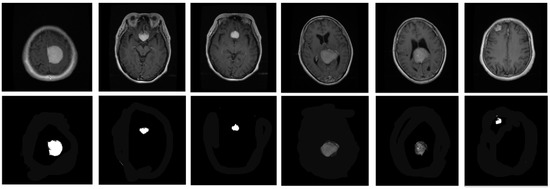

Here, P refers the random numbers for Gauss distribution. Some segmented images are shown in Figure 2.

Figure 2. Some segmented samples from dataset. (top) Original images; (bottom) Segmented images.